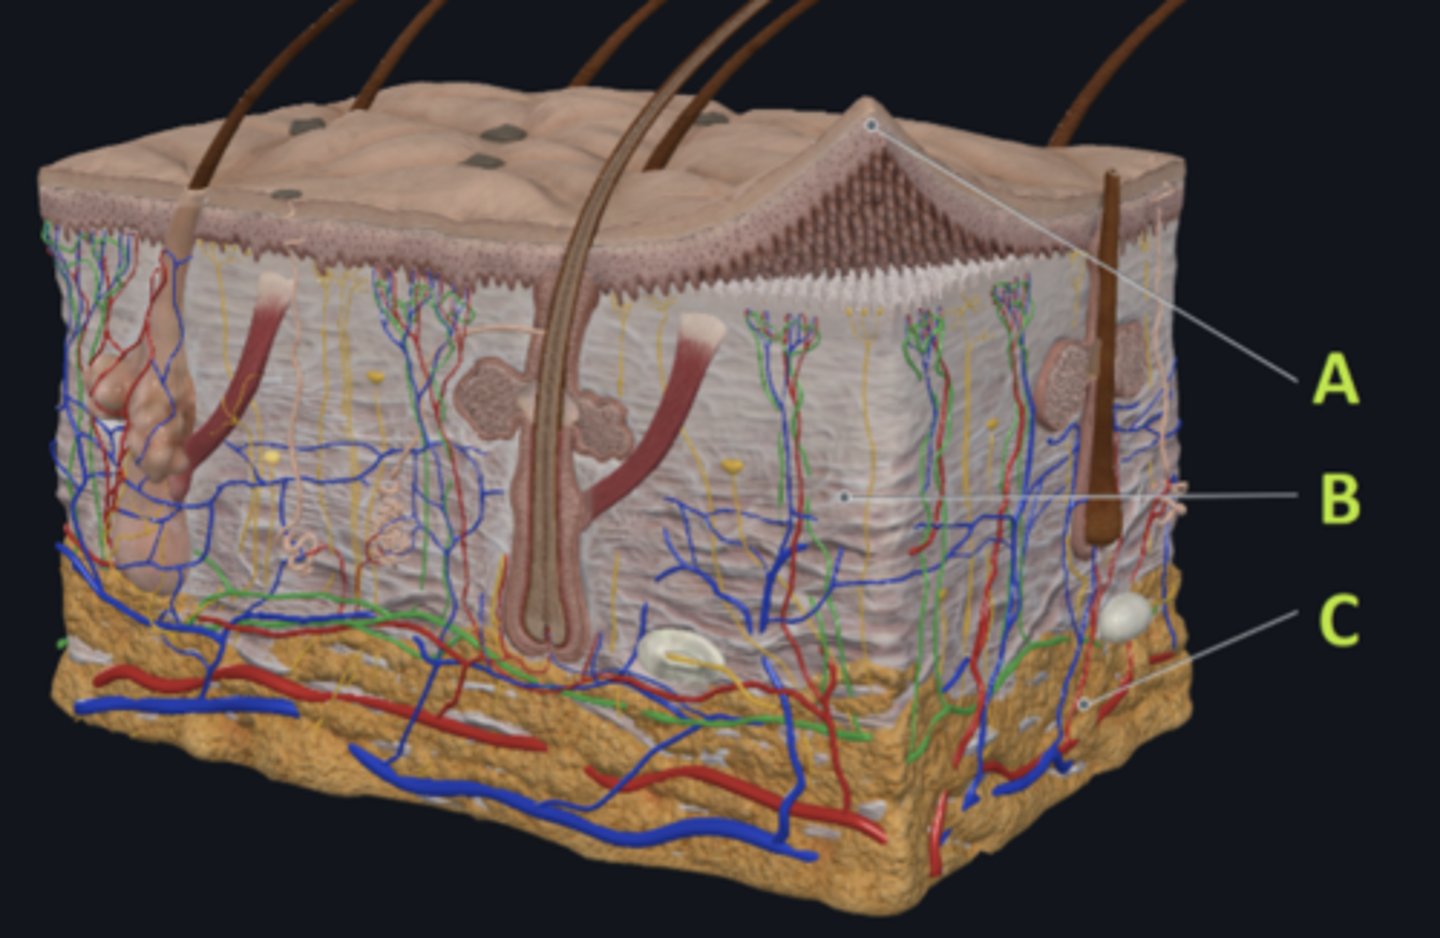

C - hypodermis

Answer the following questions based on the features indicated in the following image. Which letter indicates the administration site for subcutaneous injections?

A - epidermis

Answer the following questions based on the features indicated in the following image. Which letter indicates the administration site for topical creams and ointments?

B - Dermis

Answer the following questions based on the features indicated in the following image. Which letter indicates the administration site for the tuberculin skin test?

A - epidermis

Answer the following questions based on the features indicated in the following image. Which letter indicates a region of the skin with no nerves or blood vessels?

B - Dermis

Answer the following questions based on the features indicated in the following image. Which letter indicates the region where skin appendages (sweat glands, sebaceous glands, and hair follicles) have their roots?

Epithelial tissue

Answer the following questions based on the features indicated in the following image. Which of the four major tissue types is indicated by letter A?

Which letter indicates the administration site for insulin injections?

A

Which letter indicates the administration site for a lidocaine patch?

B

Which letter indicates the administration site for an allergy test?

B

Which letter indicates a region of the skin rich in dense, irregular connective tissue?

C

Which letter indicates the region most important for energy storage and thermal insulation?

Connective

Which of the four major tissue types is indicated by letter C?

Skin of the dorsal surface (back) of the hand

Which part of the body could the previous image represent?

Skin of the ventral surface (palm) of the hand

Skin of the dorsal surface (back) of the hand